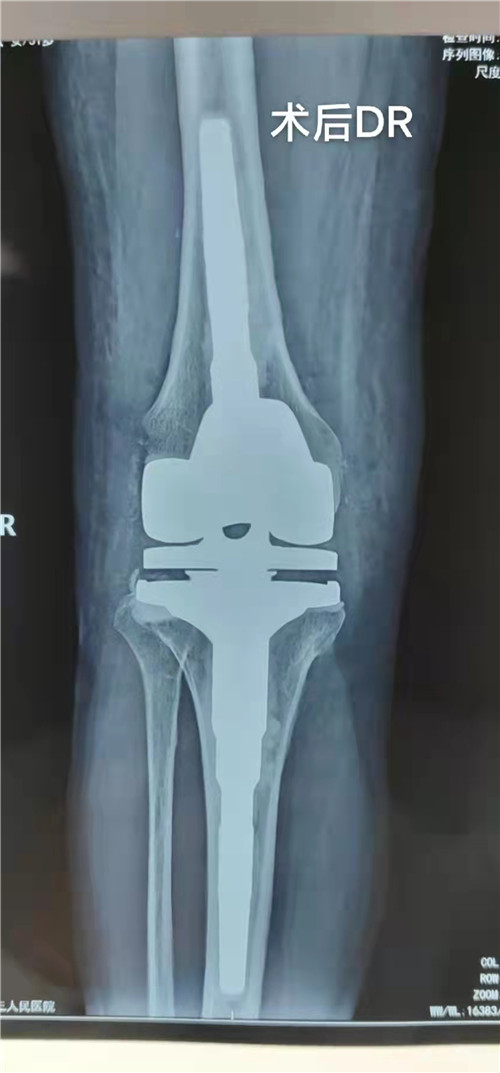

经骨一科主任邵建敏和副主任徐军志反复查阅相关资料及科室病例讨论后,与患者及家属沟通并征得同意后,建议行右膝关节铰链式人工膝关节置换手术。完善检查排除手术禁忌后于12月18日在腰硬联合麻醉下为患者行右膝关节铰链式人工膝关节置换手术,术中情况复杂:患者膝关节融合,关节间隙消失,屈曲功能丧失,只能先经验性截骨后使膝关节屈曲得到恢复,后发现膝关节截骨器械无法适配,且患者既往曾行软组织松解手术,术中腓总神经极易损伤。凭借丰富的手术经验,主刀医师在没有借助测量器械的情况下反复修整截骨最后顺利置入假体,术中膝关节活动良好。术后患者踝关节活动正常,术后3天拔管下床活动,右膝屈伸0°-30°,术后经管医师每周随诊,追踪患者功能恢复情况,指导患者功能锻炼,现患者右下肢功能恢复良好,生活质量明显提高,缓慢行走时基本与常人无异。